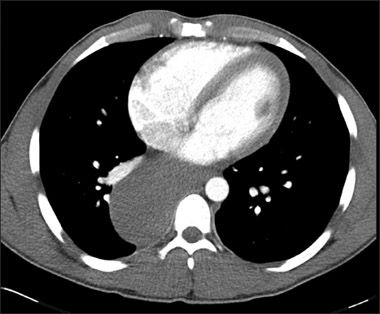

Eosinophilic ascites is an extremely rare presenting sign of hypereosinophilic syndrome.